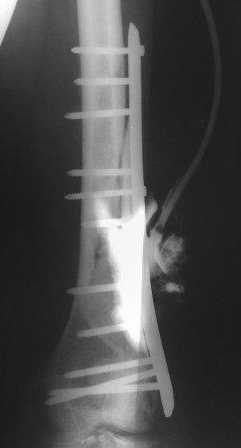

Пациент 25 лет, после автоаварии - переломы обоих бедер и обеих голеней. Поэтапно произведен

накостный остеосинтез всех сегментов( все переломы внутрисуставные в\3 голеней и н\3

бедер) Левое бедро после остеосинтеза пластиной нагноилось. Дважды производилась

открытая санация с последующим дренированием. Сейчас рана 10 х 3см с гнойным отделяемым.

Есть мысль убрать пластину, санировать рану, убрать секвестры, фиксировать в АВФ. А как вы

думаете?